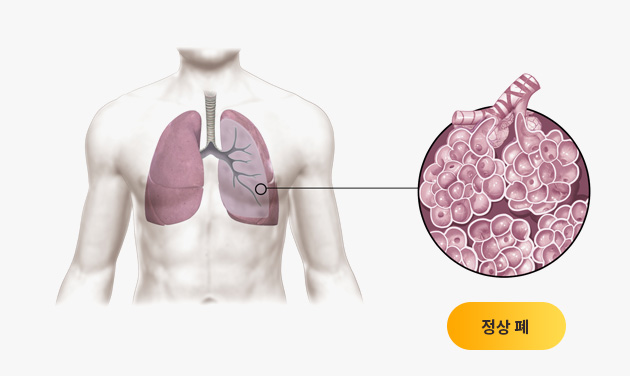

특발성폐섬유증과 같은 간질성폐질환은 예후가 좋지 못하다고 알려진 병입니다. 하지만 한약 치료를 통해 이 병을 극복하려는 노력이 진행되고 있습니다.